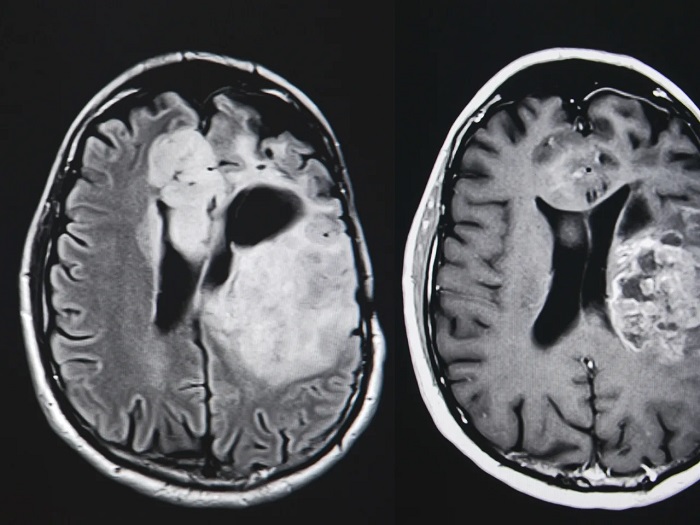

مطالعه‌ای تازه که در مجله Journal of Neuro-Oncology منتشر شده است نشان می‌دهد مصرف دوزهای بالای ویتامین B3 (نیاسین یا نیکوتین‌آمید) می‌تواند سرعت پیشرفت نوعی از تومور مغزی بسیار تهاجمی به نام گلیوبلاستوما را کاهش دهد. گلیوبلاستوما یکی از مرگبارترین سرطان‌های مغز محسوب می‌شود که درمان آن معمولاً با دشواری‌های فراوانی همراه است و میانگین طول عمر بیماران مبتلا به آن کمتر از دو سال گزارش می‌شود.